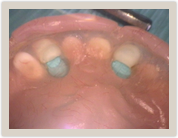

Locater Females Locater Males

P3944_ss7473cs_t P3944_ss7473zs_t

Prepped denture Locater males on Females

Dentures are snap in secured with Locater attachments. The female locaters are placed with no need for anesthetic on previously root canaled teeth. The Locater males are snapped onto the Locater females and then the Locater males are incorporated into the prepared denture with denture acrylic to create a snap on secured denture!